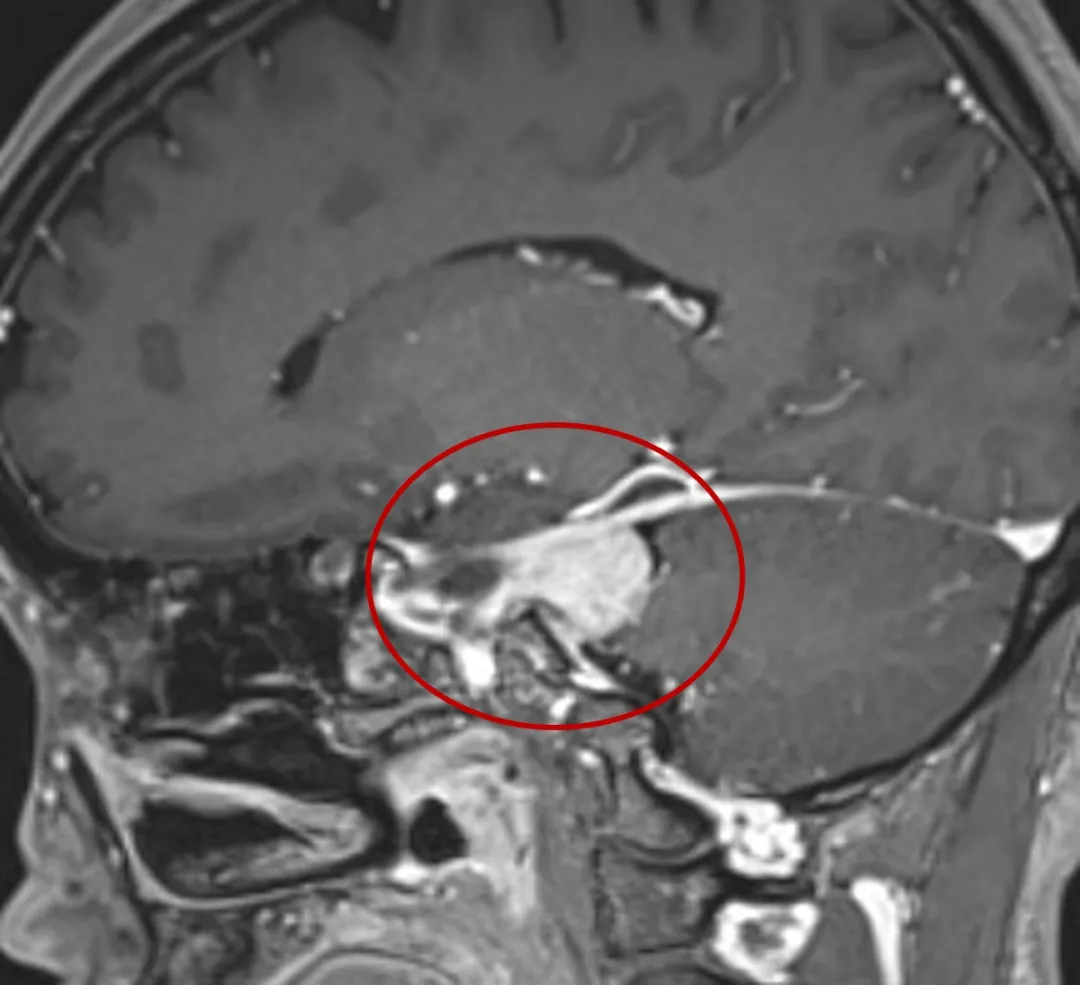

随着时间流逝,我会慢慢长大

向下生长压迫小脑

你会走路不稳、共济失调

向上发展压迫枕叶和中脑

你会偏盲、幻视和肢体瘫痪

我也可同时向上、向下生长

骑跨幕上和幕下,你则兼有上述两方面症状

由于我的快乐生长

中脑导水管和四脑室受压移位

你较早期可能出现头痛、恶心等

颅内压增高症状

冲破CPA区,结识岩斜区的朋友们

从此我不再是小小的CPA区脑膜瘤

而是大岩斜区脑膜瘤

很多重要功能神经、脑组织、血管

见了我都要退避三舍呢

脑膜瘤沿着脑膜及自然间隙增大,继续侵犯M腔,从颅后窝跨越颅中窝并侵犯海绵窦,可进一步压迫损伤视神经、动眼神经、三叉神经等

岩斜区脑膜瘤有什么了不起呢?

岩斜区脑膜瘤是起源于以岩-斜裂为中心的中上斜坡及三叉神经内侧岩骨的脑膜瘤。因岩斜区位置隐匿,解剖结构复杂,肿瘤压迫脑干与颅底神经及血管,被认为是神经外科棘手的疾病之一。手术入路较多,术后肿瘤残留率高、患者预后差等现象目前仍然存在,术中一味地追求肿瘤全切也是导致术后高病死率、高致残率的主要因素。